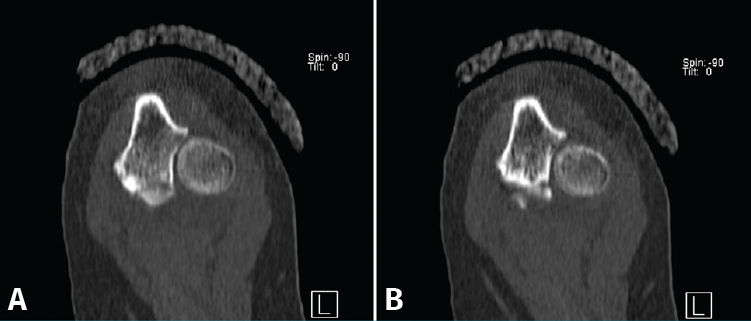

Presentamos el caso de una mujer de 46 años, diestra, sin patología crónica y que trabaja como auxiliar en una residencia geriátrica. Durante su jornada laboral sufre una caída casual presentando dolor y limitación funcional en su codo izquierdo. No presenta deformidades externas en el codo, ni lesiones vasculonerviosas. En el estudio radiológico, se sospecha una fractura de la punta de la apófisis coronoides del codo izquierdo, que correspondería, según la clasificación de Regan y Morrey, al tipo 1 (Figuras 1 y 2). Se comprueba que el codo es estable y se coloca una férula braquial, a la espera de realizar una tomografía computarizada (TC), que confirma la lesión. En la TC podemos visualizar mejor la morfología de la fractura de coronoides tanto en los cortes sagitales (Figura 3), como en los axiales (Figura 4).

Figura 4. Cortes axiales de tomografía computarizada a los 10 días de la lesión. A: fractura de la punta de la coronoides que se extiende hacia la base de la coronoides; B: fractura conminuta al nivel de la faceta anteromedial de la coronoides.